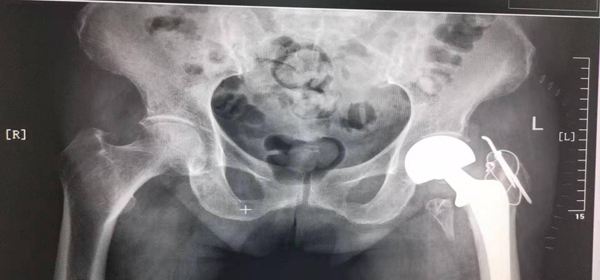

术前,创伤骨科积极完善相关检查,及时请神经内一科 呼吸内科、肾内科、心内一科、手麻科等相关科室医师会诊,协助诊治,并告知患者家属手术风险较大,家属同意手术后,创伤骨科、麻醉科、重症医学科及相关科室共同迎难而上,积极调整老人各项检查指标。9月1日,在孙奶奶病情稳定的情况下,由王争刚主任医师主刀,为孙奶奶全麻下行“左侧人工股骨头置换术”,手术时间短且顺利完成。术后,孙奶奶恢复良好,仅1周,孙奶奶就可下地站立活动,伤口顺利拆线后已出院。

术后X线片